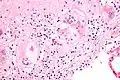

Micrograph of asteroid bodies in pulmonary sarcoidosis. H&E stain. -

Asteroid body in sarcoidosis.